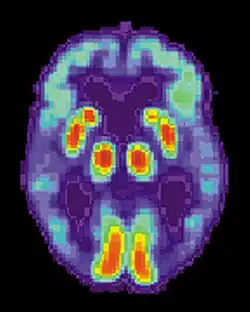

PET scan of a healthy brain - Image courtesy of US National Institute on Aging Alzheimer's Disease Education and Referral Center -

PET scan of brain with AD - Image courtesy of US National Institute on Aging Alzheimer's Disease Education and Referral Center

Alzheimer's disease (AD) is a progressive, degenerative and fatal brain disease, in which cell to cell connections in the brain are lost. Alzheimer's disease is the most common form of dementia.[2] Globally approximately 1–5% of the population is affected by Alzheimer's disease.[3] Women are disproportionately affected by Alzheimer's disease. The evidence suggests that women with AD display more severe cognitive impairment relative to age-matched males with AD, as well as a more rapid rate of cognitive decline.[4]